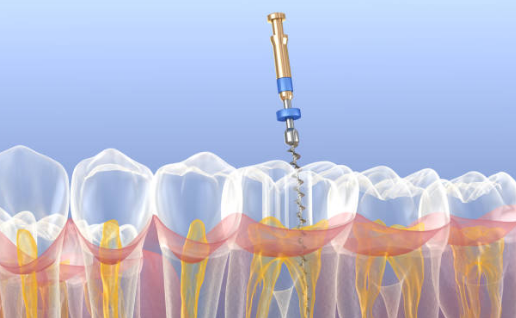

ENDODONCJA – LECZENIE KANAŁOWE

Leczenie endodontyczne, czyli kanałowe, polega w głównej mierze na ratowaniu zęba ogarniętego w dużej mierze zaawansowaną próchnicą. Polega na usunięciu z kanałów korzeniowych zmienionej zapalnie lub martwej miazgi, dezynfekcji i poszerzeniu kanałów zębowych oraz ich szczelnym wypełnieniu. Takie rozwiązanie uniemożliwia późniejsze osiedlanie się bakterii w systemie kanałów korzeniowych. Dzięki użyciu mikroskopu stomatologicznego w nowoczesnej endodoncji, szanse powodzenia w uleczeniu chorego zęba, są o wiele większe.

Uratowanie zębów, które wstępnie zostały zakwalifikowane do ekstrakcji czy wyrwania, jest o wiele łatwiejsze i możliwe do wykonania. Po prawidłowo przeprowadzonym leczeniu kanałowym, możliwa jest odbudowa korony zęba i przewrócenie jego podstawowych funkcji w jamie ustnej.

Dodatkowym atutem nowoczesnego leczenia endodontycznego, jest możliwość zastosowania mikroskopu stomatologicznego, który pozwala na uzyskanie doskonałej widoczności pola zabiegowego, co umożliwia wysoką precyzję i skuteczność leczenia zębów. Użycie mikroskopu pozwala na skuteczne znalezienie dodatkowych ujść kanałów, usunięcie złamanych narzędzi, dostrzeżenie perforacji oraz pęknięć dna komory i pozwala na powtórne, skuteczne leczenie kanałowe (Re-endo).

Podczas leczenia kanałowego pod mikroskopem, zaczynamy od diagnostyki radiologicznej, która umożliwia poznanie całego uzębienia pacjenta. Zabieg wykonujemy w znieczuleniu, co gwarantuje pełen komfort pacjenta i możliwie najbezpieczniejszą formę leczenia. Pole zabiegowe, izolowane jest za pomocą koferdamu, a kanały korzeniowe opracowywane są mechanicznie. Prowadzimy dokładne odkażanie kanałów przy pomocy ultradźwięków. Wypełniamy następnie szczelnie najskuteczniejszym klinicznie materiałem, czyli ciekłą gutaperką.

W zależności od stopnia destrukcji tkanek zębowych i miazgi, odbudowa całego zęba, polega w głównej mierze na:

– wykonaniu wypełnienia światłoutwardzalnego

– wzmocnieniu korzenia wkładem z włókna szklanego i odbudowie materiałem światłoutwardzalnym

– wzmocnieniu korzenia wkładem włókna szklanego i odbudowie koroną protetyczną

ENDODONCJA

Leczenie endodontyczne, czyli kanałowe, polega w głównej mierze na ratowaniu zęba ogarniętego w dużej mierze zaawansowaną próchnicą. Polega na usunięciu z kanałów korzeniowych zmienionej zapalnie lub martwej miazgi, dezynfekcji i poszerzeniu kanałów zębowych oraz ich szczelnym wypełnieniu. Takie rozwiązanie uniemożliwia późniejsze osiedlanie się bakterii w systemie kanałów korzeniowych. Dzięki użyciu mikroskopu stomatologicznego w nowoczesnej endodoncji, szanse powodzenia w uleczeniu chorego zęba, są o wiele większe.

Uratowanie zębów, które wstępnie zostały zakwalifikowane do ekstrakcji czy wyrwania, jest o wiele łatwiejsze i możliwe do wykonania. Po prawidłowo przeprowadzonym leczeniu kanałowym, możliwa jest odbudowa korony zęba i przewrócenie jego podstawowych funkcji w jamie ustnej.

Dodatkowym atutem nowoczesnego leczenia endodontycznego, jest możliwość zastosowania mikroskopu stomatologicznego, który pozwala na uzyskanie doskonałej widoczności pola zabiegowego, co umożliwia wysoką precyzję i skuteczność leczenia zębów. Użycie mikroskopu pozwala na skuteczne znalezienie dodatkowych ujść kanałów, usunięcie złamanych narzędzi, dostrzeżenie perforacji oraz pęknięć dna komory i pozwala na powtórne, skuteczne leczenie kanałowe (Re-endo).

Podczas leczenia kanałowego pod mikroskopem, zaczynamy od diagnostyki radiologicznej, która umożliwia poznanie całego uzębienia pacjenta. Zabieg wykonujemy w znieczuleniu, co gwarantuje pełen komfort pacjenta i możliwie najbezpieczniejszą formę leczenia. Pole zabiegowe, izolowane jest za pomocą koferdamu, a kanały korzeniowe opracowywane są mechanicznie. Prowadzimy dokładne odkażanie kanałów przy pomocy ultradźwięków. Wypełniamy następnie szczelnie najskuteczniejszym klinicznie materiałem, czyli ciekłą gutaperką.

W zależności od stopnia destrukcji tkanek zębowych i miazgi, odbudowa całego zęba, polega w głównej mierze na:

– wykonaniu wypełnienia światłoutwardzalnego

– wzmocnieniu korzenia wkładem z włókna szklanego i odbudowie materiałem światłoutwardzalnym

– wzmocnieniu korzenia wkładem włókna szklanego i odbudowie koroną protetyczną